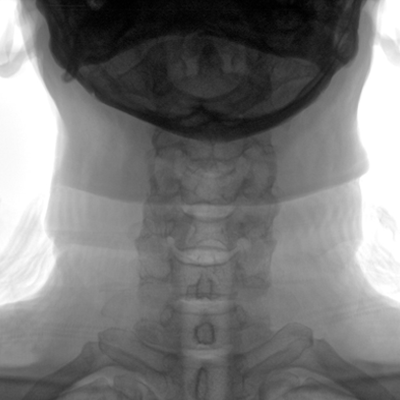

大尺寸動(dòng)態(tài)平板探測器,高DQE、低噪聲、圖像清晰。采用多分辨率圖像增強處理技術(shù),不同部位不同圖像處理算法,滿(mǎn)足客戶(hù)多樣化的需求。

采用智能變頻脈沖透視技術(shù),優(yōu)化圖像質(zhì)量的同時(shí)降低輻射劑量,呵護醫患健康

多角度自由旋轉,滿(mǎn)足患者復雜擺位需求。